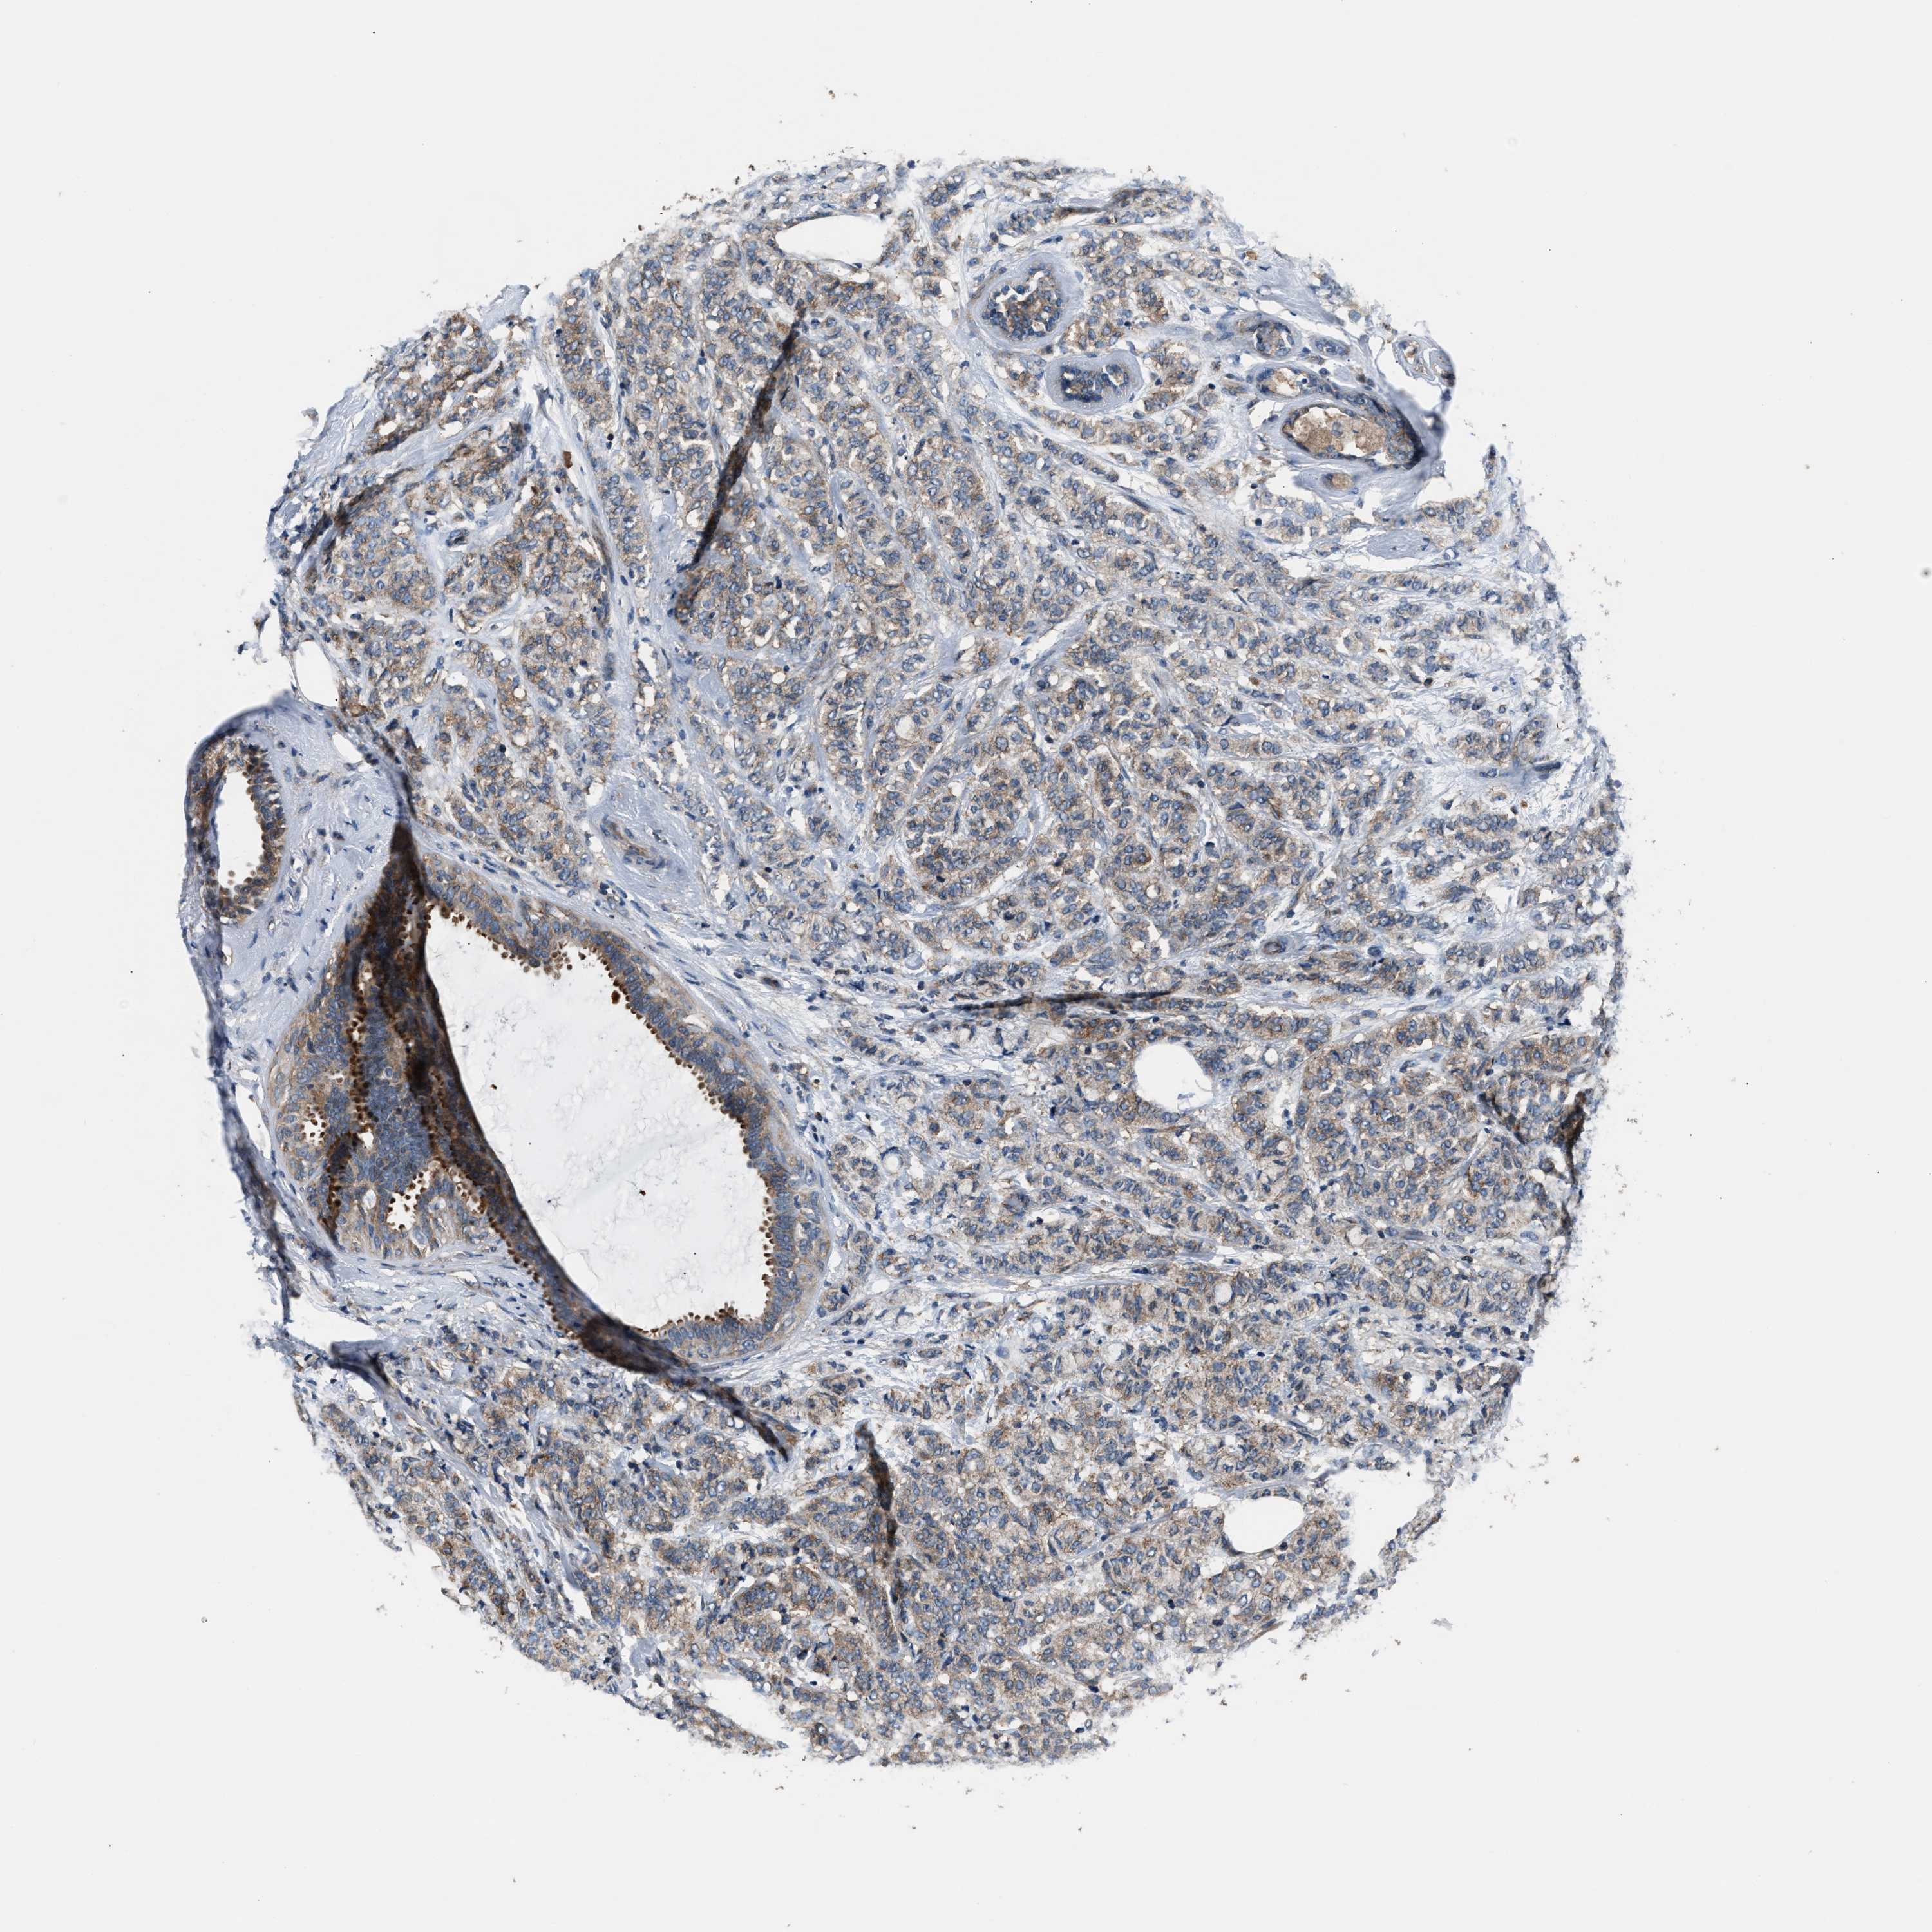

CANCER BREAST CANCER Show tissue menu

BRCA TCGA BRCA VALIDATION PROTEIN EXPRESSION

Breast cancer

Human cancer

Breast invasive carcinoma